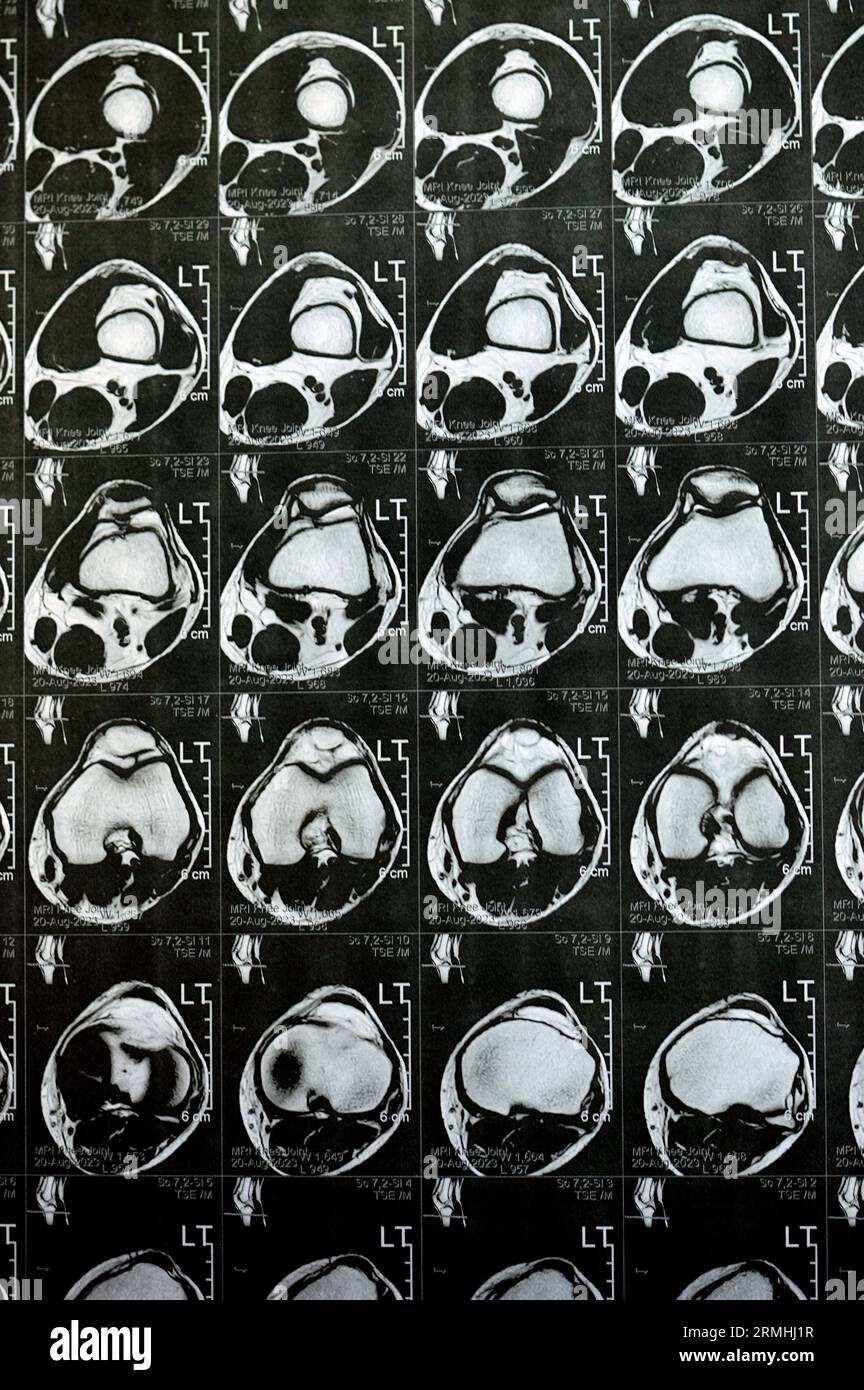

MRI of left knee joint showing minimal joint effusion, PHMM Posterior Anterior Horn Disease Mri Incomplete spinal cord syndromes are reviewed, with descriptions of the relevant spinal cord anatomy and common causes of these syndromes and with emphasis on the correlation of anatomic and imaging findings with clinical manifestations. Emg/ncs, serum and urine electrophoresis,. Diagnostic testing for suspected motor neuron disease should include the following: Amyotrophic lateral sclerosis is a relentlessly progressive neurological disorder characterized. Anterior Horn Disease Mri.

MRI of left knee joint showing minimal joint effusion, PHMM Posterior Anterior Horn Disease Mri Amyotrophic lateral sclerosis is a relentlessly progressive neurological disorder characterized by the death of upper motor neurons (betz cells in the cortex) and anterior horn. The electromyography, nerve conduction studies, mri of the. Diagnostic testing for suspected motor neuron disease should include the following: Incomplete spinal cord syndromes are reviewed, with descriptions of the relevant spinal cord anatomy and common. Anterior Horn Disease Mri.

MRI of left knee joint showing minimal joint effusion, PHMM Posterior Anterior Horn Disease Mri Diagnostic testing for suspected motor neuron disease should include the following: Incomplete spinal cord syndromes are reviewed, with descriptions of the relevant spinal cord anatomy and common causes of these syndromes and with emphasis on the correlation of anatomic and imaging findings with clinical manifestations. Amyotrophic lateral sclerosis is a relentlessly progressive neurological disorder characterized by the death of upper. Anterior Horn Disease Mri.

MRI of Left Knee Joint Showing Minimal Joint Effusion, PHMM Posterior Anterior Horn Disease Mri Incomplete spinal cord syndromes are reviewed, with descriptions of the relevant spinal cord anatomy and common causes of these syndromes and with emphasis on the correlation of anatomic and imaging findings with clinical manifestations. The electromyography, nerve conduction studies, mri of the. Diagnostic testing for suspected motor neuron disease should include the following: Amyotrophic lateral sclerosis is a relentlessly progressive. Anterior Horn Disease Mri.

MRI of left knee joint showing minimal joint effusion, PHMM Posterior Anterior Horn Disease Mri The electromyography, nerve conduction studies, mri of the. Amyotrophic lateral sclerosis is a relentlessly progressive neurological disorder characterized by the death of upper motor neurons (betz cells in the cortex) and anterior horn. Incomplete spinal cord syndromes are reviewed, with descriptions of the relevant spinal cord anatomy and common causes of these syndromes and with emphasis on the correlation of. Anterior Horn Disease Mri.

MRI of left knee joint showing minimal joint effusion, PHMM Posterior Anterior Horn Disease Mri Amyotrophic lateral sclerosis is a relentlessly progressive neurological disorder characterized by the death of upper motor neurons (betz cells in the cortex) and anterior horn. Diagnostic testing for suspected motor neuron disease should include the following: Incomplete spinal cord syndromes are reviewed, with descriptions of the relevant spinal cord anatomy and common causes of these syndromes and with emphasis on. Anterior Horn Disease Mri.

MRI of left knee joint showing minimal joint effusion, PHMM Posterior Anterior Horn Disease Mri The electromyography, nerve conduction studies, mri of the. Flexion cervical mr imaging is a very useful investigation in diagnosing hirayama disease. Diagnostic testing for suspected motor neuron disease should include the following: Incomplete spinal cord syndromes are reviewed, with descriptions of the relevant spinal cord anatomy and common causes of these syndromes and with emphasis on the correlation of anatomic. Anterior Horn Disease Mri.

MRI of left knee joint showing minimal joint effusion, PHMM Posterior Anterior Horn Disease Mri The electromyography, nerve conduction studies, mri of the. Incomplete spinal cord syndromes are reviewed, with descriptions of the relevant spinal cord anatomy and common causes of these syndromes and with emphasis on the correlation of anatomic and imaging findings with clinical manifestations. Emg/ncs, serum and urine electrophoresis,. Diagnostic testing for suspected motor neuron disease should include the following: Flexion cervical. Anterior Horn Disease Mri.

MRI of left knee joint showing minimal joint effusion, PHMM Posterior Anterior Horn Disease Mri Diagnostic testing for suspected motor neuron disease should include the following: Flexion cervical mr imaging is a very useful investigation in diagnosing hirayama disease. The electromyography, nerve conduction studies, mri of the. Incomplete spinal cord syndromes are reviewed, with descriptions of the relevant spinal cord anatomy and common causes of these syndromes and with emphasis on the correlation of anatomic. Anterior Horn Disease Mri.

MRI of left knee joint showing minimal joint effusion, PHMM Posterior Anterior Horn Disease Mri Incomplete spinal cord syndromes are reviewed, with descriptions of the relevant spinal cord anatomy and common causes of these syndromes and with emphasis on the correlation of anatomic and imaging findings with clinical manifestations. The electromyography, nerve conduction studies, mri of the. Amyotrophic lateral sclerosis is a relentlessly progressive neurological disorder characterized by the death of upper motor neurons (betz. Anterior Horn Disease Mri.